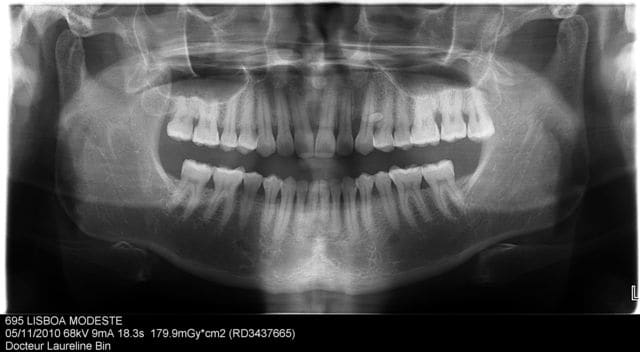

en clinique épulis entre 22 et 23 et hyperplasie en palatin de 23.

je pense que la chirurgie sera nécessaire, mais c'est quoi selon vous?

Tu ne saura ce que c'est qu'après avoir ouvert, voire même après anapath si besoin. Ça semble vaguement conoïde : donc odontome possible, mais l'image n'a pas la même radio-opacité que les dents (semble plus dense). L'image se superpose à la racine de 23 mais masque celle de 24 : résorption ? L'image de poche paro en mésial de 23 et les lésions gingivales que tu décris me semblent également atypiques pour un odontome.

Est-ce que vous voyez une image radio-opaque ronde entre les apex de 11/21 ?

pour moi ça ressemble à un odontome